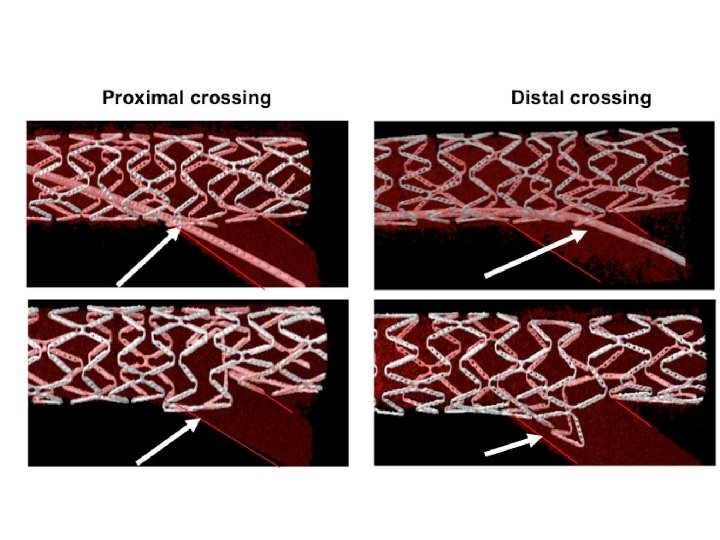

Provisional stenting strategy 1. Both branches are wired starting with the most difficult one 2. MB is stented (stent sized according to MB distal reference) and SB wire is jailed 3. The stent is post-dilated using the Proximal Optimization Technique (POT) to maximize stent apposition 4. Stent is now well apposed proximally, while the SB is partially covered by scaffolding 5. MB wire is pulled back and reinserted through the most distal strut of the SB opening scaffold 6. Jailed wire is removed and re-inserted in the distal MB (with a formed loop at the distal end) 7. The Kissing Balloon inflation is done to optimize side branch flow and access 8. Final result (if suboptimal, can then place additional stents)